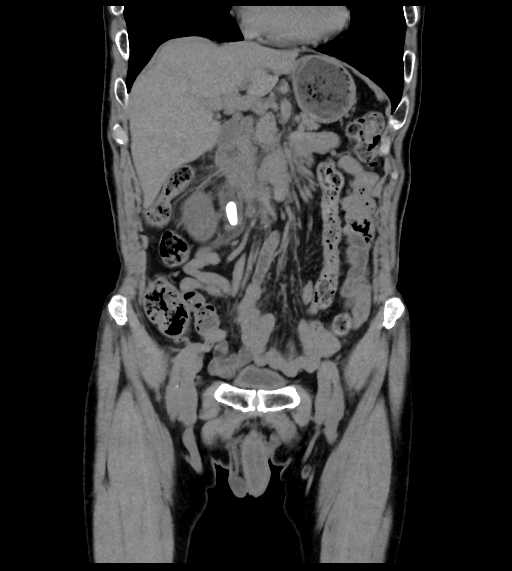

CT検査

内科領域

腹部

尿管結石